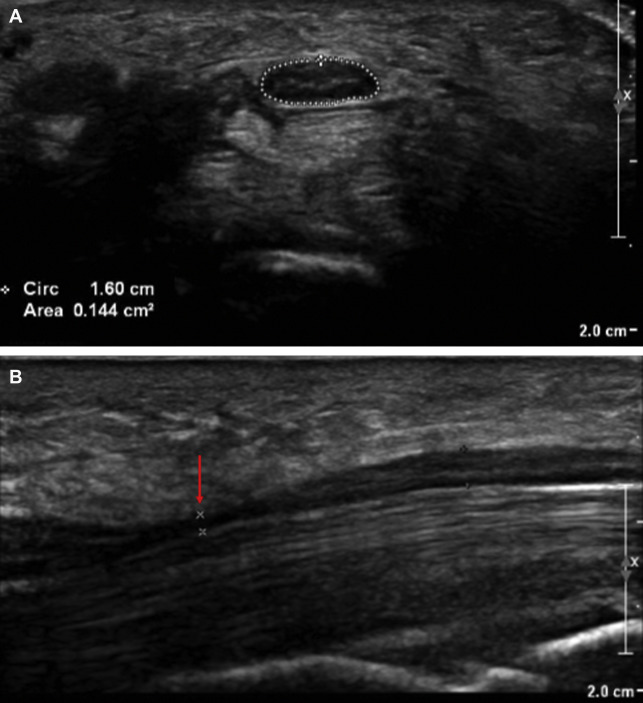

Elements of interest when assessing a peripheral nerve include nerve size (measured as cross-sectional area and sometimes diameter), echogenicity, and fascicular enlargement. Increased vascularity may be seen on Doppler. Anomalous structures are noted and may include cysts, tumors, intruding muscle, penetrating arteries, and foreign bodies.

In general, an entrapped nerve will demonstrate an enlarged cross-sectional area (CSA) proximal and distal to its compressive site. Loss of fascicular detail and increased vascularity may be present. Entrapment may be caused by passage through a fibro-osseous tunnel; enlargement or malpositioning of nearby structures (such as muscle or bone); postoperative changes such as scarring, foreign bodies, and hardware; and various other causes. The nerve of interest must always be imaged at noncompressive sites for comparison, and various ratios exist for determining carpal tunnel syndrome and ulnar neuropathy at the elbow. If the nerve is diffusely enlarged at noncompressive sites, an inflammatory or hereditary neuropathy should be considered.

Carpal tunnel syndrome